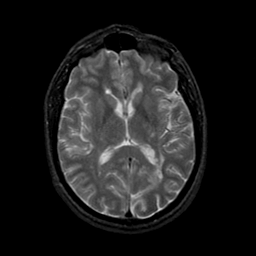

MR Study #23, January 26, 1992 -- Slice #27